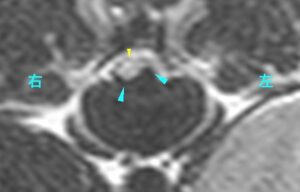

[T11-12横断像、T2強調画像]

MRI検査の所見から、「椎間板ヘルニアおよび脊髄軟化症」と診断